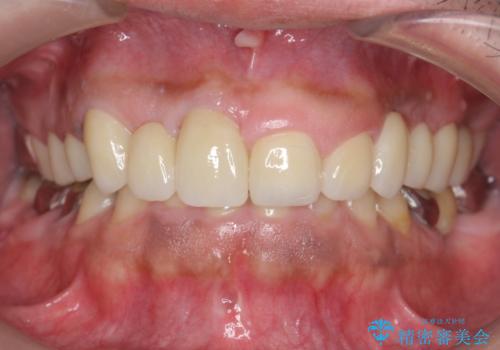

オールセラミッククラウン ブリッジによる欠損歯の補綴

インプラントは希望されなかったため、左側は1番から7番のロングスパンブリッジによる補綴を行いました。

今回用いたオールセラミッククラウンは、ジルコニアフレームという白い素材の上にセラミックを盛っているため審美性が非常に高いのが特徴です。

またジルコニアは人工ダイヤモンドの材料にも使われているほど高い強度を持っており、そのためオールセラミッククラウンは審美性だけでなく、奥歯やブリッジの補綴も可能とするクラウンです。